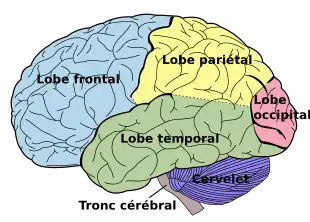

Les lobes externes du cerveau humain. Sont aussi dessinés le cervelet en bleu et le tronc cérébral en noir qui sont des structures nerveuses distinctes du cerveau proprement dit.

En anatomie, chacun des deux hémisphères du cerveau est divisée en plusieurs lobes dont quatre sont dits externes et deux sont dits internes.

Les quatre lobes externes, situés immédiatement sous les os du crâne sont, d'avant en arrière :

- Le lobe frontal, situé juste derrière le front au-dessus des yeux (en bleu sur la figure) ;

- Le lobe temporal, situé au-dessus de l'oreille légèrement en arrière et en dessous du lobe frontal (en vert sur la figure) ;

- Le lobe pariétal, situé en arrière du lobe frontal (en jaune sur la figure) ;

- Le lobe occipital, situé au niveau de l'occiput, c'est-à-dire la partie la plus arrière du crâne (en rose sur la figure).